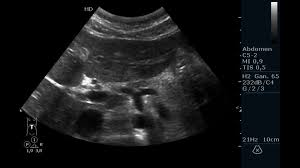

Patient presented SOB to the ED. During your eval you perform a cardiac US. What view is displayed? What sign is present? Name 2 diff diagnoses

What is A4CH

What is McDonnell sign

What is PH, PE

Caution, McDonnell sign has been classically attributed to PE but it actually happens due to RV ischemia since RV is not used to high after load. Thus any pathology that can affect RV after load can cause it. It has also been observed in cases of inferior ischemia